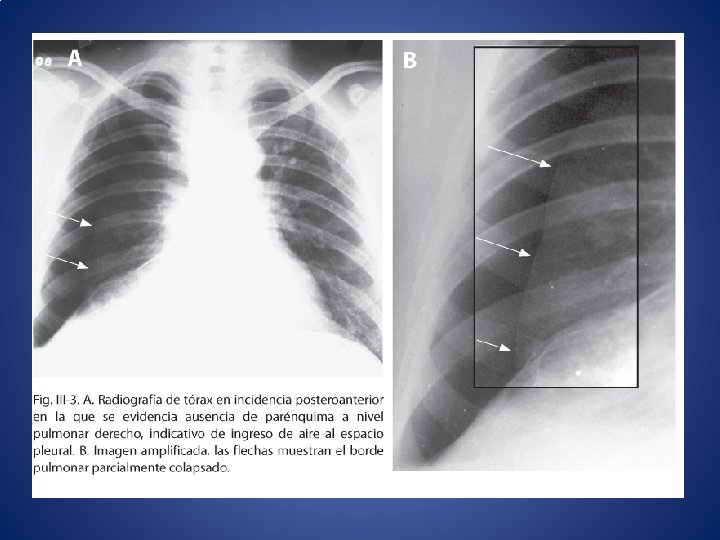

Paciente masculino de 35 años, luego de accidente automovilístico presenta herida penetrante en el

Paciente masculino de 35 años, luego de accidente automovilístico presenta herida penetrante en el tórax, observándose orificio con entrada de aire. • • a. Tipos de neumotórax • b. Presiones en el sistema respiratorio • c. Consecuencias del neumotórax • d. Tratamiento • e. Trampa de agua